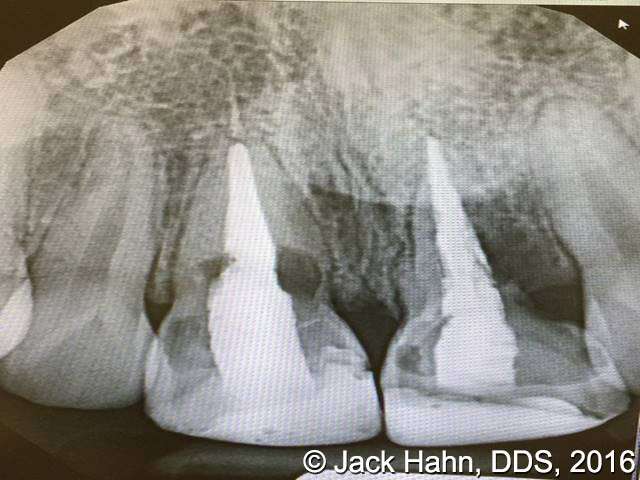

CASE #4 Trauma Case – Central Incisors Internal / External Resorption

Implants, that replace failed endo- or perio-compromised teeth, have a MUCH higher success rate with laser decontamination of the osteotomy site. LightScalpel laser surgical and perio laser tips ensure excellent access to extraction socket for the optimum removal of granulation tissue and socket decontamination (protocol involves manual curettage of the socket with alternating rinsing and lasing).

The patient, a 17-year-old female was involved in a water slide accident 3 years ago. As a result, both central incisors were avulsed and an endodontist replanted them. Both teeth exhibited internal and external resorption. Dr. Hahn extracted both central incisors, removed all the root fragments and sanitized the sites with the LightScalpel laser which also eliminated any granulation tissue. The #8 area was prepared to place a Hahn 4.3×13 Implant and #9 was prepared for a Hahn 3.5×13. 3mm tall Hahn healing abuts were placed slightly below the gingival-tissue level to help develop an emergence profile when at the restoration time in 4 months. Upon seeing the x-ray, Dr. Hahn tightened the healing abutment on #9 to be sure that it was completely seated on the implant. 45nucm. stability was achieved on both implants. He then placed some bone putty to seal any openings. To be on the safe side, he decided to place a temporary partial instead of immediate temporary prosthetics.